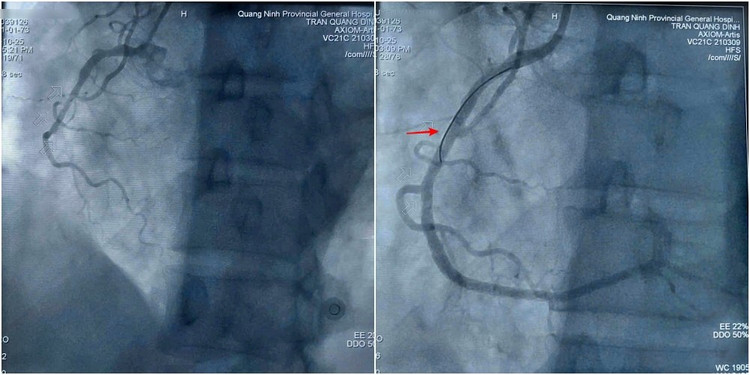

Hình ảnh trước và sau can thiệp đặt stent tái thông mạch vành cho bệnh nhân Q. Ảnh BV

Sau khi hội chẩn và giải thích rõ tình trạng cho gia đình, ca can thiệp được đội ngũ bác sĩ khoa Phẫu thuật và Can thiệp Tim mạch tiến hành khẩn trương ngay sau đó. Kết quả chụp mạch cho thấy tổn thương nặng 3 thân động mạch vành, trong đó hẹp tắc hoàn toàn động mạch vành phải. Kíp can thiệp tiến hành nong bóng và đặt 2 stent để tái thông động mạch bị hẹp tắc. Hình ảnh chụp kiểm tra sau thủ thuật cho thấy stent thông tốt, dẫn máu trở lại nuôi tim.